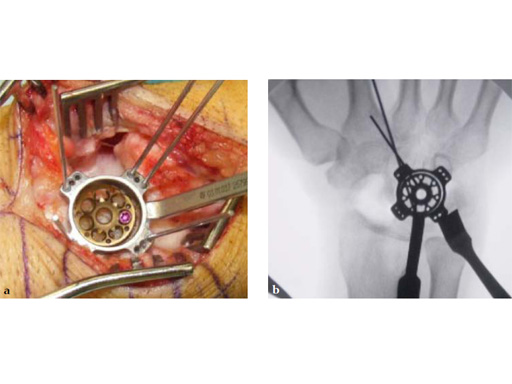

Fig 3ab Bone debridement. Guide positioning and fixation.

Fig 3c Bone debridement. Guide positioning and fixation.

Fig 4c Once the carpal junctions have been putting closer by the new reduction-compression guide, reaming is done.

Fig 5ab Plate positioning and fixation. The combined VA-locking-standard guide allows drilling in the appropriate direction.

Fig 5cd Plate positioning and fixation. The combined VA-locking-standard guide allows drilling in the appropriate direction.